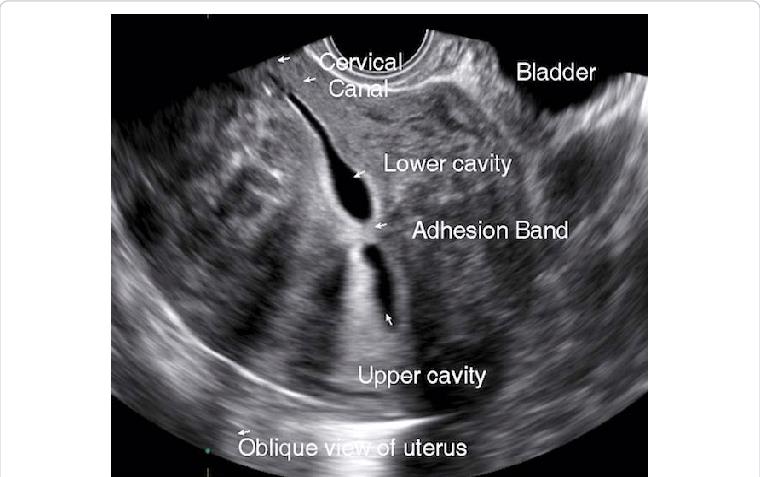

Adhesions (“hyperechoic band-like lesions”)

- Provider to document findings appropriately per individual practice guidelines. Finding should be described by their appearance and no diagnosis given as no pathology has been obtained (I.e. “filling defects” or “hyperechoic lesion”) with measurement provided. Filling defects- note size, location and what the findings suggest. Examples:

- Intracavity filling defect (note size/location), and additional contrast required to distend cavity.